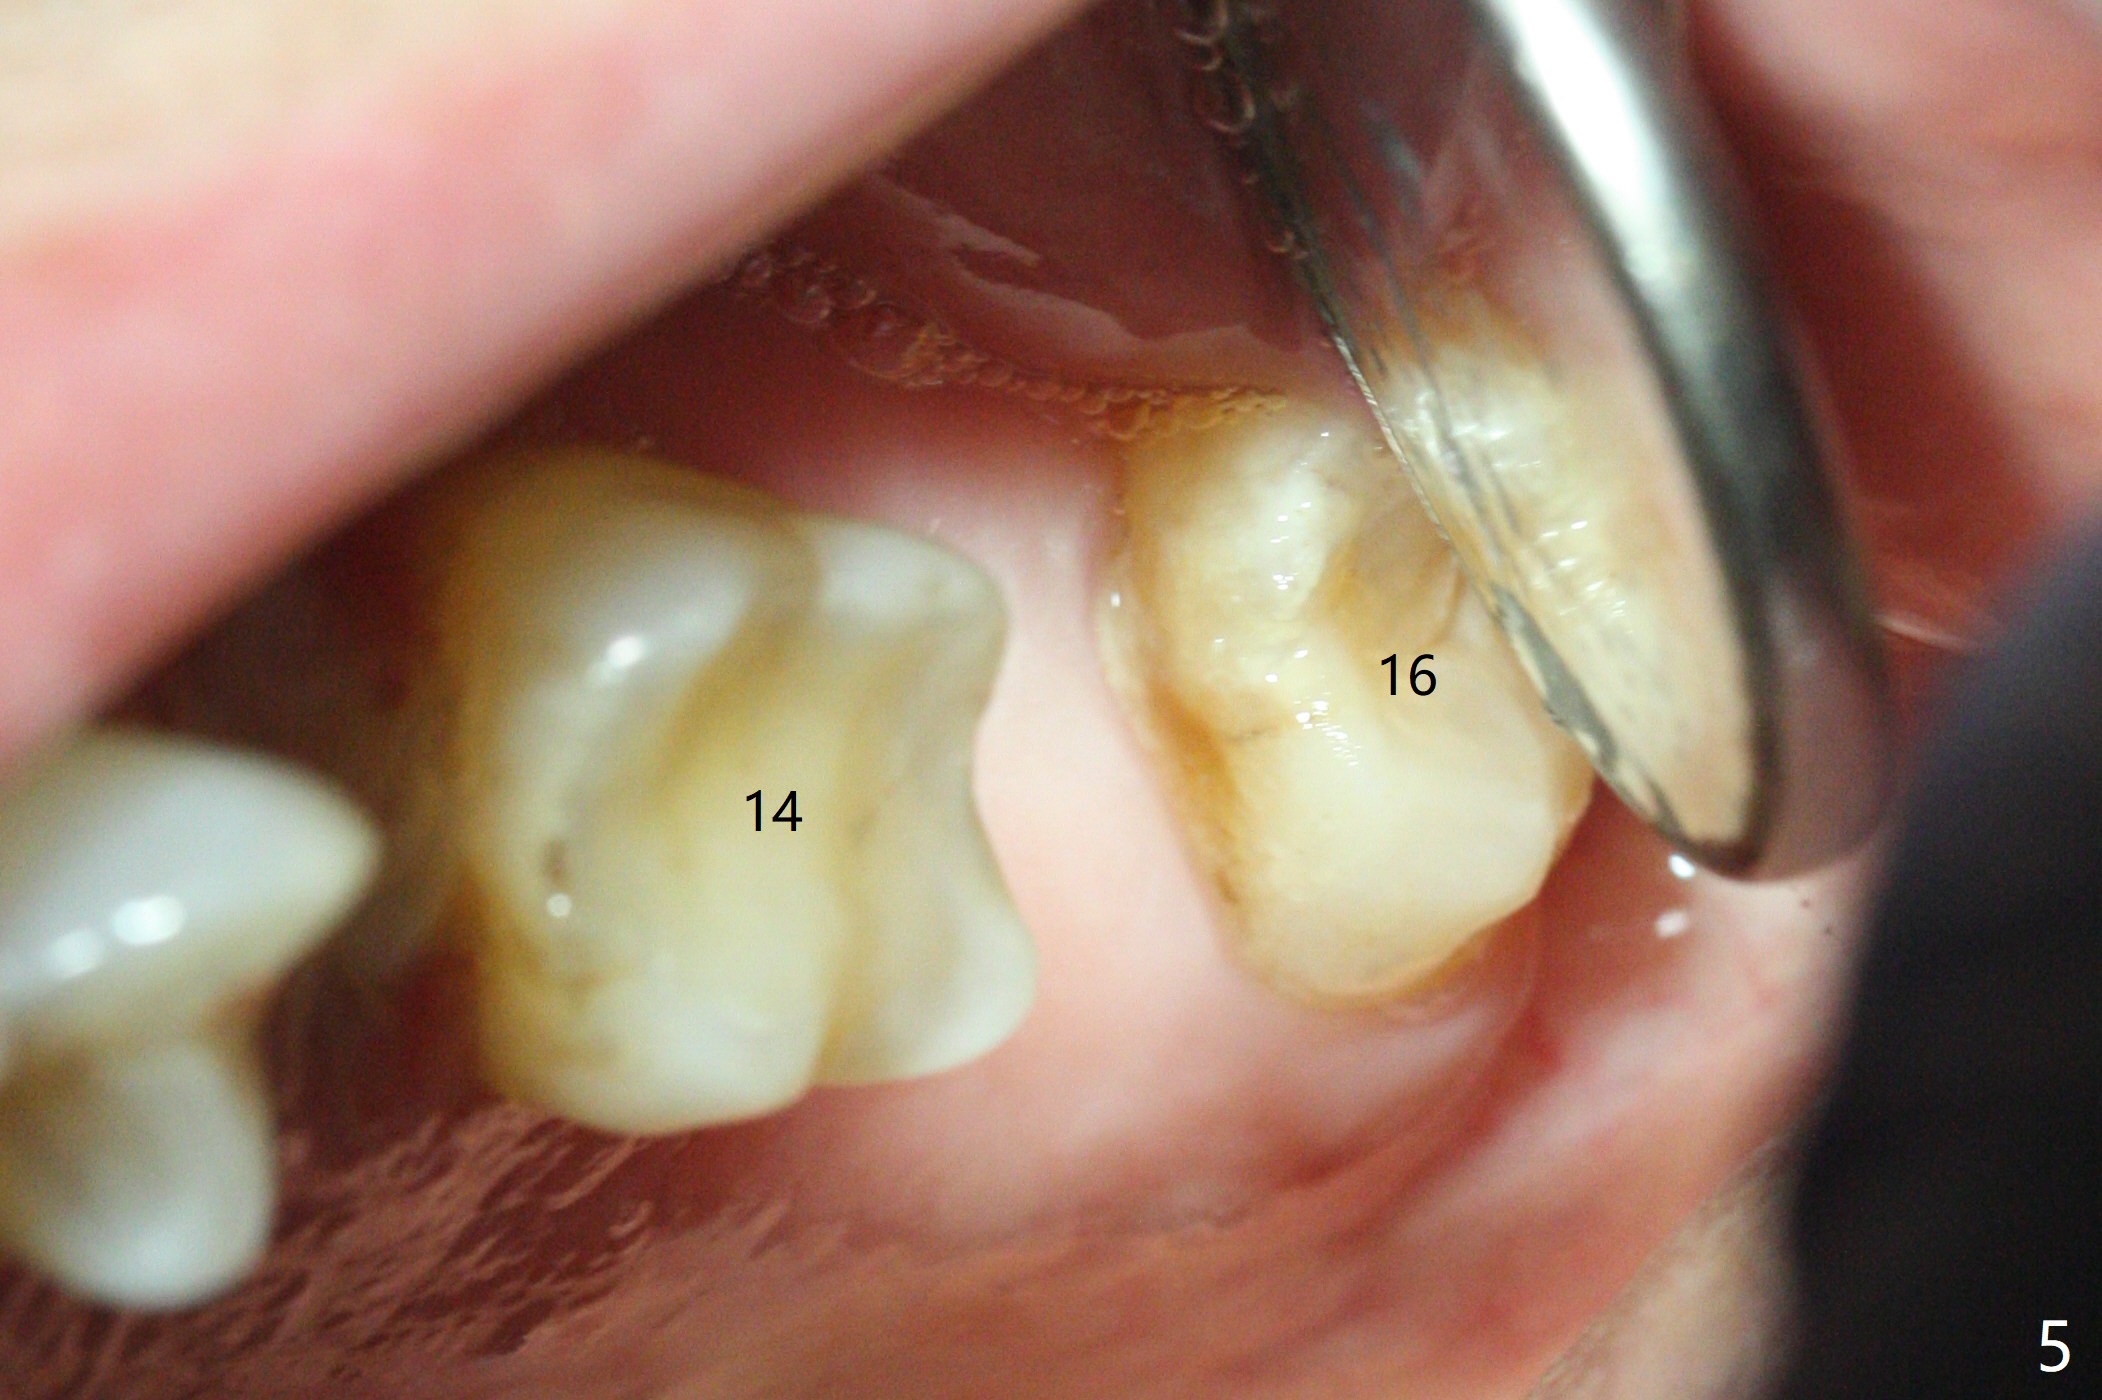

A 65-year-old man cracks 3 teeth in ~2 years (Fig.1,2 (#4,13,15)). The tooth #4 is symptomatic after RCT (Fig.1); it appears that the buccal canal is incompletely filled (data not shown). In fact an exam 1 month later shows that the symptomatic tooth is #2 (crack), while #4 is salvageable (Fig.8). The tooth #13 has palatal subgingival fracture with severe pain (Fig.2 with palatal defect). In fact the title of this case is incorrect). After extraction, allograft is placed (Fig.3 *) with 6-month membrane. In fact the bone graft is not packed into the apex of the socket; a condenser should have been used. The patient returns 3 days postop before leaving abroad. The 6-month membrane remains in place (Fig.4), while the ridge at #15 is minimally atrophic (Fig.5). The coronal lamina dura becomes indistinct 5 months postop (Fig.6). The bone graft remains in the socket. The distoapical portion of a 4x11.5 mm implant may be in the sinus (Fig.7).